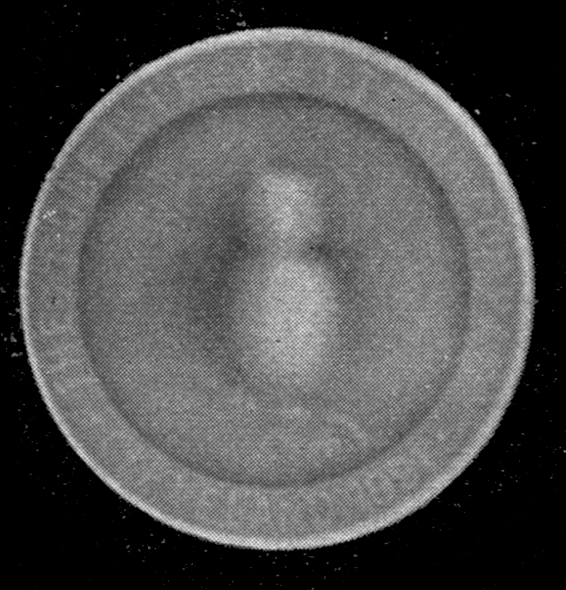

Fig. 1.—Head.